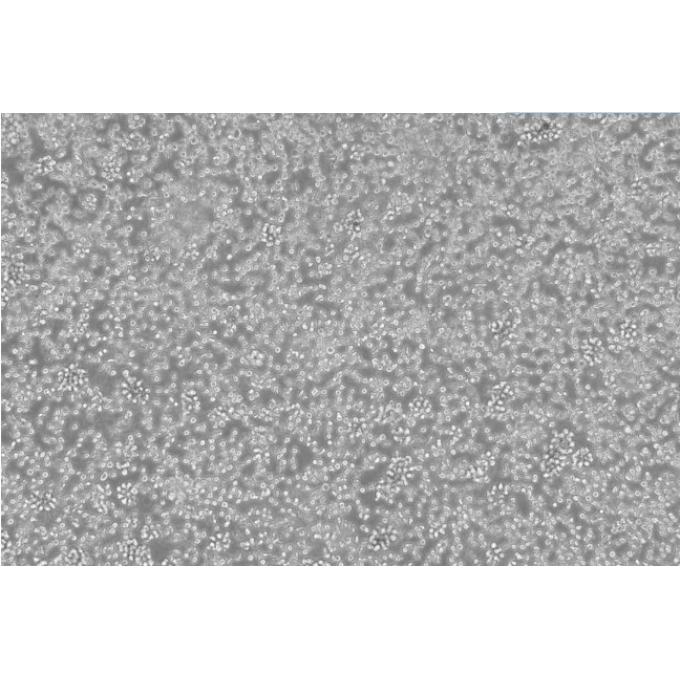

Bel-7402 细胞;人肝癌细胞

• 形态特征:上皮样

• 细胞描述: BEL-7402细胞株是1974年从临床肝癌手术标本中建立的。 细胞群体倍增时间为20小时。 移植到处理过的wistar大鼠中的能形成肿瘤结节。 细胞形态呈上皮样细胞。 在电子显微镜下亦显示上皮细胞所具有的桥粒和张力原纤维,与临床肝癌细胞相似。 分瓶培养第四天时,其有丝分裂指数约为7%。 BEL-7402细胞的染色体数为不足三倍体,有一个异常的近端着丝点染色体。 间接免疫荧光法测BEL-7402细胞内的AFP为阳性反应。 LDH同工酶谱显示与成年人肝细胞不同,而与人胚肝及临床肝癌相近。